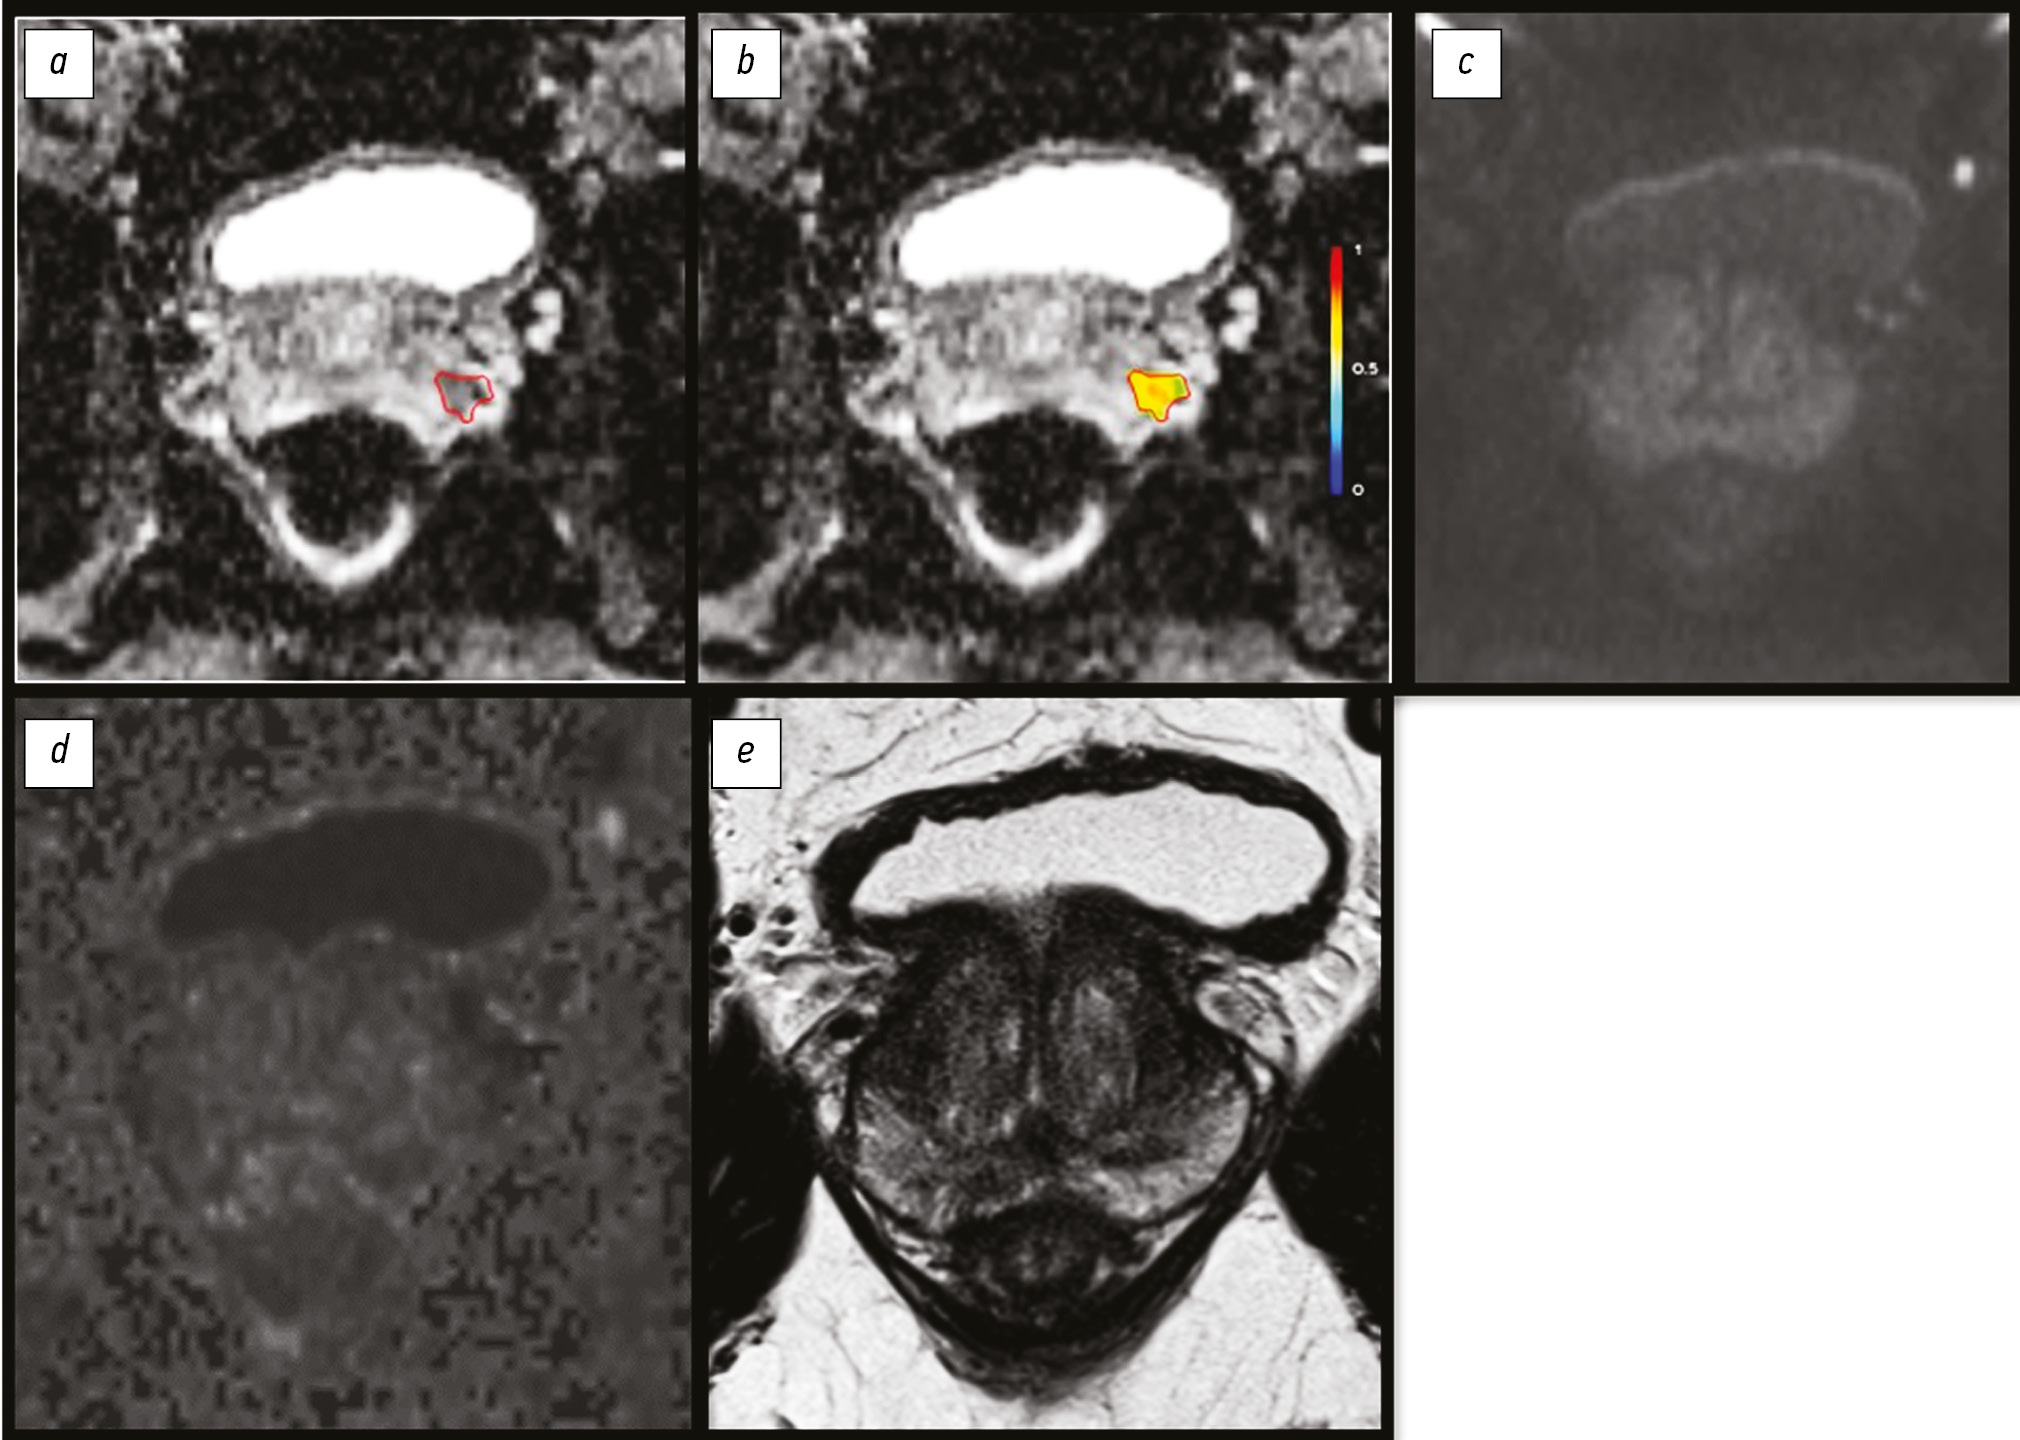

Additionally, numerous studies have reported conflicting results regarding texture analysis of transient zone (TZ) cancer. Thus, A. Wibmer et al. [16] did not reveal significant differences in the textural characteristics of diffusion-weighted images between tumors in the PZ and those in the transition zone. An example of entropy estimation is presented in Figure 2.

Fig. 2. Segmentation and evaluation of the entropy of the tumor focus of the transition zone of the prostate

Note. a, Map of the measured diffusion coefficient (MDC) of magnetic resonance imaging (MRI) of the prostate gland of a 65-year-old patient with a prostate tumor (Gleason 3 + 4) shows an area of reduced MDC (red outline; posterior segment of the transition zone of the middle part of the left lobe of the gland). Prostate biopsy performed 6 days after MRI; b, a heat map of a normalized textural characteristic (entropy); c, diffusion-weighted image (DWI), b-factor 900 mm/s2, pathological focus is not visualized; d, DWI, calculated b-factor 1400 mm/s2, pathological focus is not visualized; e, T2-weighted image, the pathological focus is not visualized.

In T2-weighted images, only correlation and contrast were significant characteristics in both TZ and PZ texture analysis [16]. In their work involving 26 patients, H.S. Sidhu et al. [22] have revealed that kurtosis and entropy extracted from diffusion- and T1-weighted images were significant tumor predictors. The values of kurtosis decreased after resection of the tumor focus from the cut.